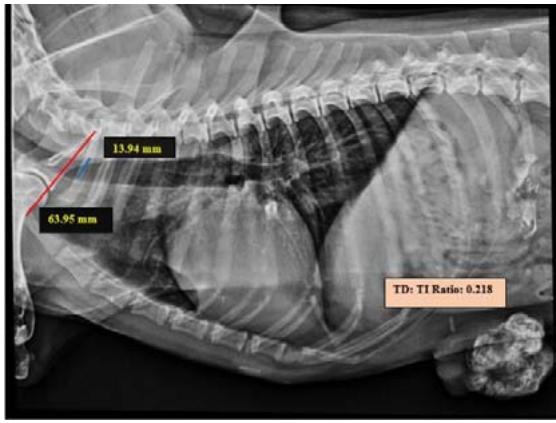

Tracheal Diameter: Tracheal Inlet (TD: TI) ratio was calculated by recording the diameter of the trachea at the level of the thoracic inlet and the inner diameter of the thoracic inlet (Fig 1). Cardiothoracic ratios (CTR) were calculated by dividing the largest width of the thorax by chest depth on radiographs (Fig 3). On a dorsoventral/ventrodorsal radiograph, the width of the thorax was measured as the distance between the medial borders of the eight ribs (Fig 4). The depth was assessed on the right lateral radiographic view from the dorsal margin of the xiphoid process to the ventral margin of the vertebral body, with the electronic calipers aligned perpendicular to the vertebral column. The Vertebral heart score was calculated according to Buchanan and Bucheler, 1995 (Fig 2).

Tracheal diameter: Thoracic inlet ratios was calculated from lateral radiographs in all animals by the method proposed by Harvey and Fink (1982). Three of the animals with mammary neoplasm had a ratio of less than 0.2, indicating tracheal hypoplasia, whereas the TD: TI ratio in superficial neoplasm affected animals was in the normal range, indicating normal tracheal confirmation. The relationship between TD: TI ratio and neoplasm conditions was not yet reported. The finding of tracheal hypoplasia in this study could be related to other physiological factors. The exact measurements of the tracheal diameter were challenging with radiography owing to the absence of sharp luminal borders due to overlying soft tissues as opined by Fingland et al. (1995).

Fig.1: Skiagram showing measurement of TD: TI ratio from the right lateral view